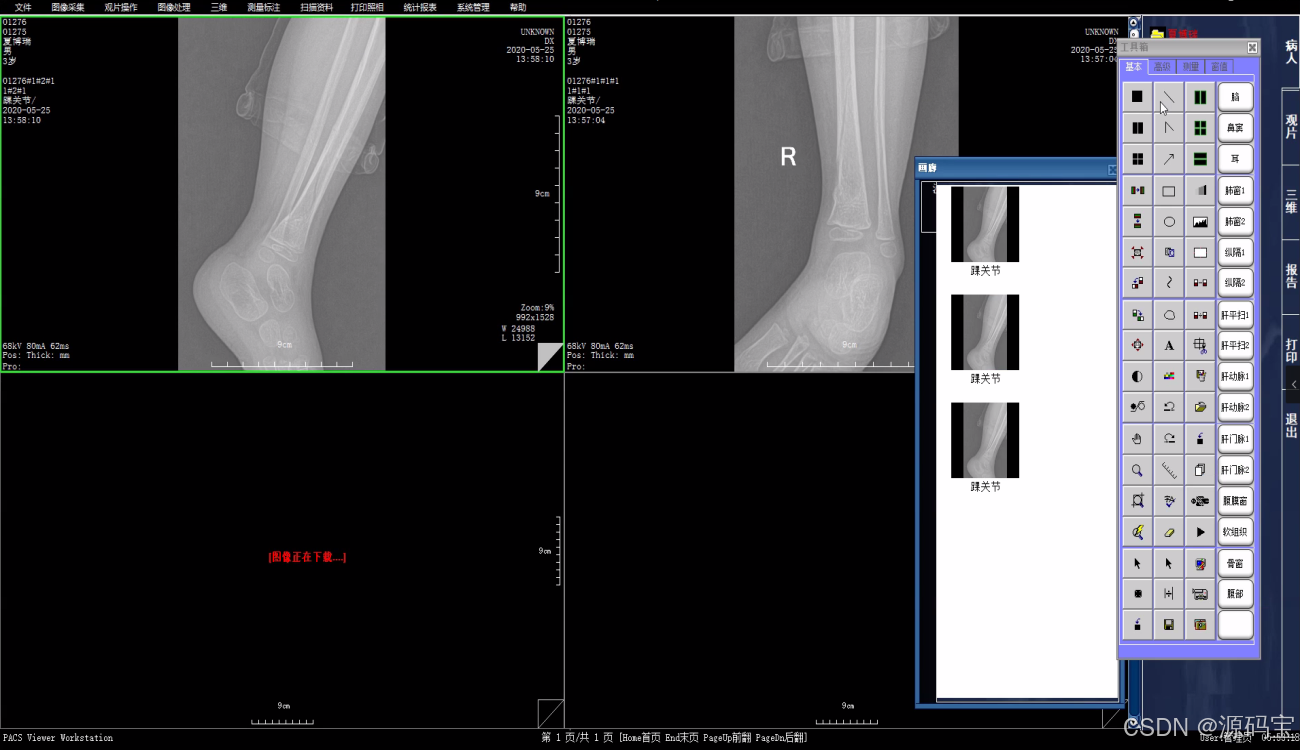

医学影像归档与通讯系统(PACS)系统,是一套适用于从单一影像设备到放射科室、到全院级别等各种应用规模的医学影像归档与通讯系统。PACS集患者登记、图像采集、存档与调阅、报告与打印、查询、统计、刻录等功能为一体,有效地实现了对海量医学影像的高效管理,各科室间各种图文资源的高度共享,在医院数字化建设过程中扮演重要角色。

5、强大的图像处理功能,方便医生对动静态图像进行反复观察、比较、研究。

9、可预设布局、尺寸等特性的胶片打印功能,支持图片组合成像。